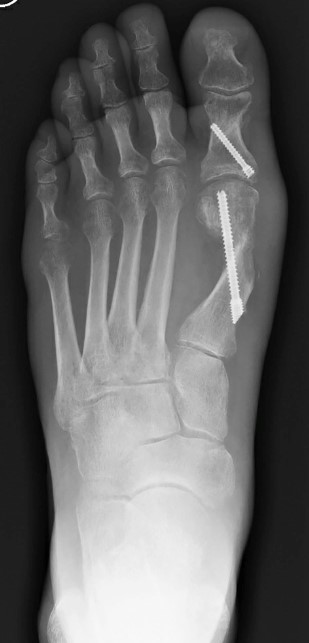

L’imaging serve per studiare in dettaglio la deformità dell’alluce valgo e comprendere quale sia la cura più appropriata, se conservativa o chirurgica, sulla base dell’evolutività.

Deve includere: una radiografia dei piedi IN CARICO, meglio se bilaterale. È fondamentale che le radiografie siano eseguite in carico (stando in piedi) per studiare l’anatomia mentre lavora, e bilaterale, perché i due piedi sono spesso simili anche se solo uno fa male, offrendo informazioni preziose per il confronto.

La procedura chirurgica prevede, tramite l’utilizzo di tre mini-incisioni di pochi millimetri, la resezione parziale della cipolla, una osteotomia e il bloccaggio della stessa tramite una o due viti.